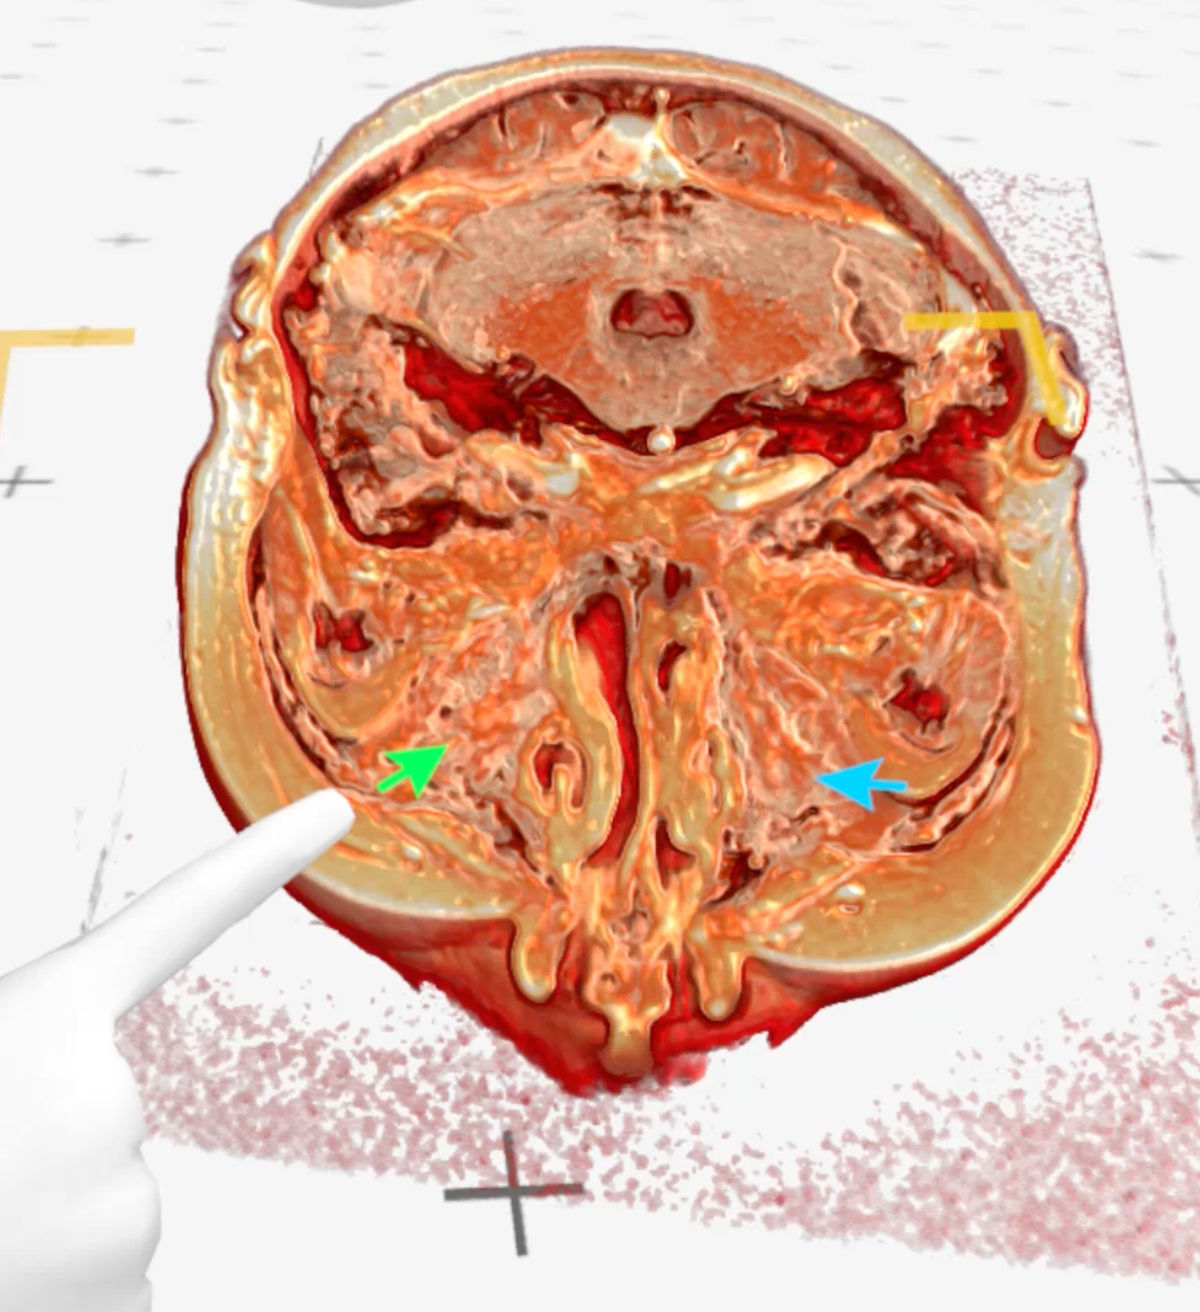

These lesions were visualized with volumetric 3D-rendering of the CT and MRI images with Medical Imaging XR software (MedicalHolodeck, Switzerland), which allowed for better evaluation of the pathologically altered craniofacial anatomy (Fig. 6-9).

Figure 9. Medical Imaging XR 3D-rendered MRI shows maxillary sinuses completely filled with soft tissue (green arrow - right maxillary sinus, blue arrow - left maxillary sinus).